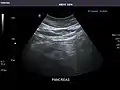

- Pancreas

Pancreas: Visualized portions unremarkable.